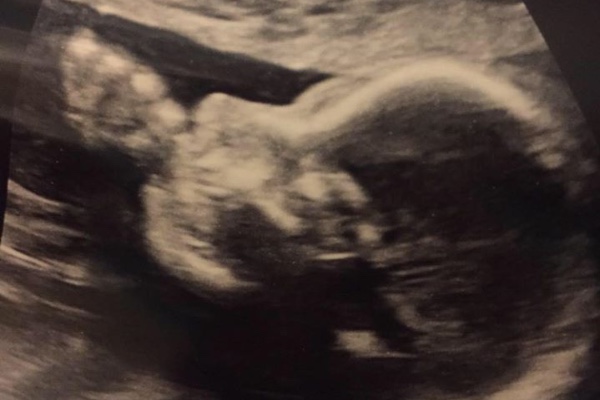

Baby Kendrick has been diagnosed with Spina Bifida. This means that he could potentially have issues with the motor skills in his lower extremities, neurological function, and incontinence. Kendrick will have to have at least one surgery to enclose the opening on his back (part of his spinal cord is only covered by a thin membrane). He may also need additional surgery to put in a shunt and to correct any additional issues that may arise. He will also need to be in physical therapy to help strengthen his legs. Although we still don’t know exactly how life will be for Kendrick, we do know that he has a ton of support from his friends and family to help keep him strong.